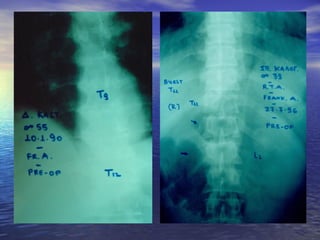

ΑΑππεειικκοοννιισσττιικκόόςς έέλλεεγγχχοοςς

ΑΑκκττιιννοολλοογγιικκόόςς έέλλεεγγχχοοςς

οολλοοκκλλήήρροουυ ττηηςς ΣΣπποοννδδυυλλιικκήήςς ΣΣττήήλληηςς

• ΠΠρροοσσθθιιοο--οοππιισσθθίίωωςς

• ΠΠλλααγγίίωωςς

ΑΑκκττιιννοολλοογγιικκόόςς έέλλεεγγχχοοςς οολλοοκκλλήήρροουυττηηςς ΣΣπποοννδδυυλλιικκήήςς ΣΣττήήλληηςς • ΠΠρροοσσθθιιοο--οοππιισσθθίίωωςς • ΠΠλλααγγίίωωςς